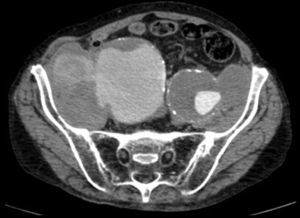

Paciente varón de 86 años, hipertenso en tratamiento con 2 fármacos, con historia de dolor lumbar con irradiación crural derecha de varios meses de evolución que se había controlado parcialmente con tratamiento sintomático. Su reumatólogo le había prescrito RM dorsolumbar que no llegó a realizarse ya que el paciente acudió antes a urgencias por aumento de la intensidad del dolor. En la analítica, hemoglobina 8,4g/dl, LDH 318 U/l, creatinina 1,29mg/dl, PCR 6,16mg/dl, VSG 24mm/h y leve hipoproteinemia. Ausencia de signos de inestabilidad hemodinámica. Se realizó una TC abdominopélvica con contraste por vía intravenosa que muestra aneurismas ilíacos aislados bilaterales>6cm (fig. 1) con rotura contenida del derecho (fig. 2), que desplazaba el músculo psoas (fig. 3) y horadaba el hueso ilíaco ipsolateral (fig. 4). El paciente es sometido a by-pass aortobifemoral pero lamentablemente fallece en el postoperatorio.

Los aneurismas ilíacos aislados, sin aneurisma aórtico asociado, son raros1. Son relativamente difíciles de identificar, ya que hasta un 40% de ellos se pueden presentar con rotura2. La tasa de incidencia de causas extraespinales de ciática es baja3. Igualmente, el aneurisma roto crónico constituye una entidad peculiar. Todas estas circunstancias se aúnan para que el diagnóstico, la mayoría de las veces, sea erróneo y tardío4. Suele tratarse de una rotura laterodorsal hacia las inserciones anteriores del psoas que contiene el hematoma, evitando la extravasación masiva pero no la infiltración de las raíces del plexo lumbosacro, lo que origina un dolor crónico lumbar con irradiación al miembro inferior5, siendo esta su presentación más frecuente6. El diagnóstico puede realizarse con TC abdominal7, pudiendo también visualizarse en la RM lumbar (corte parasagital)7,8. En cualquier momento de la evolución, el aneurisma puede sufrir una rotura aguda secundaria4. Este caso sirve para recordarnos, en nuestra práctica diaria, que la causa aneurismática puede estar implicada en los síntomas de ciática9.